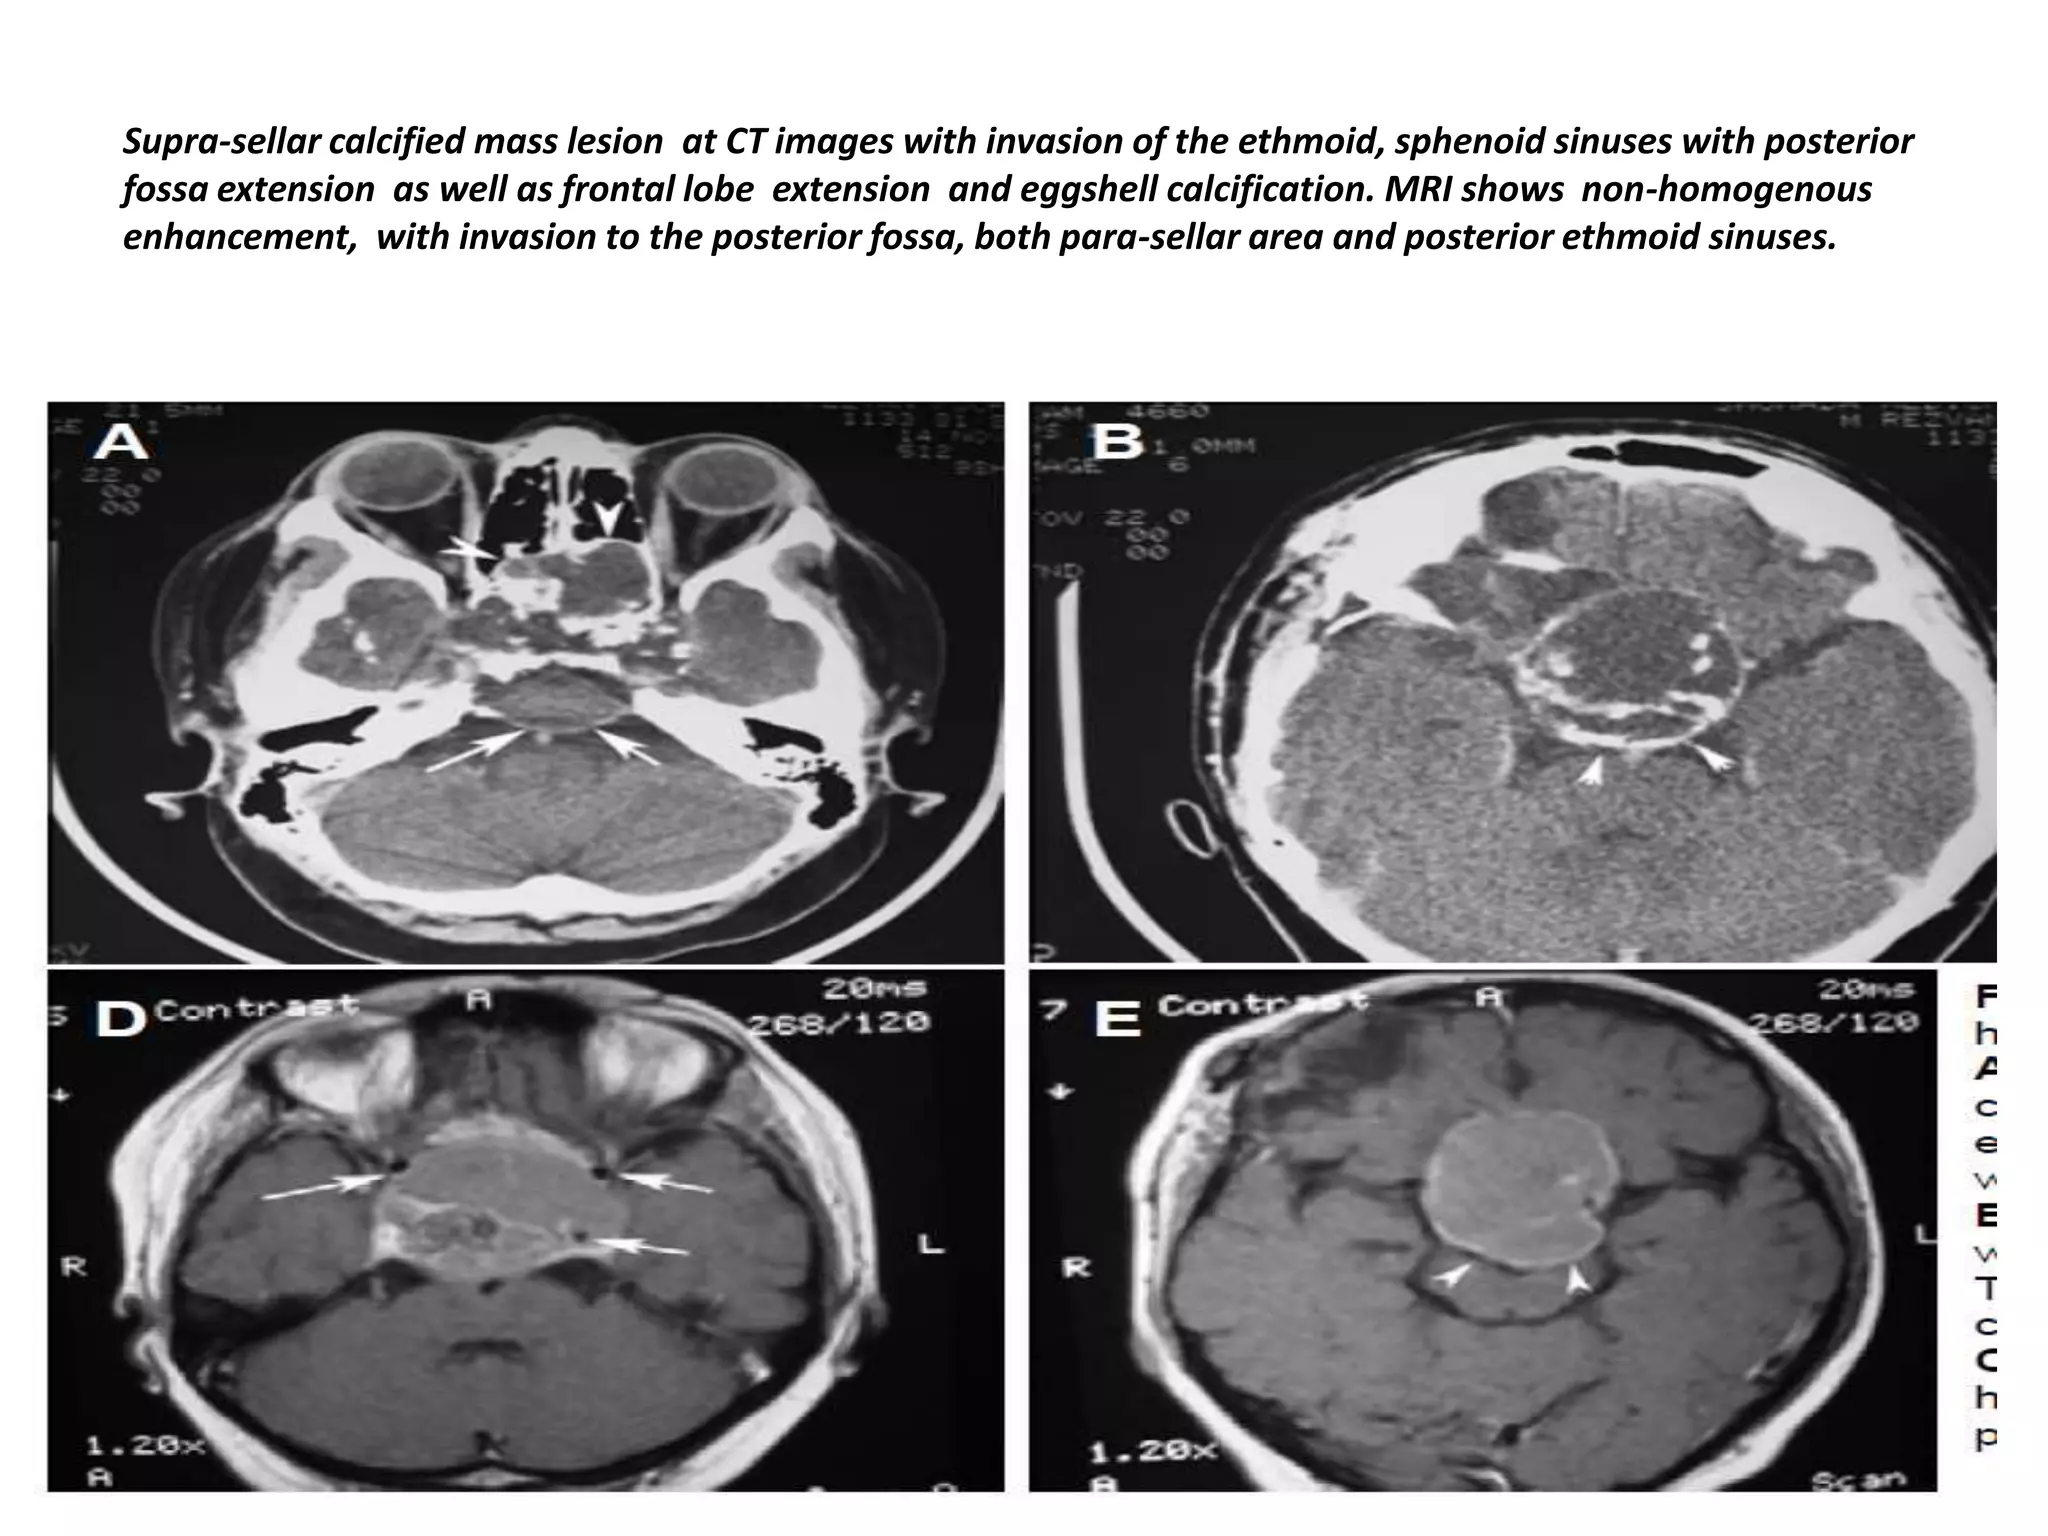

Supra-sellar calcified mass lesion at CT images with invasion of the ethmoid, sphenoid sinuses with posterior

fossa extension as well as frontal lobe extension and eggshell calcification. MRI shows non-homogenous

enhancement, with invasion to the posterior fossa, both para-sellar area and posterior ethmoid sinuses.